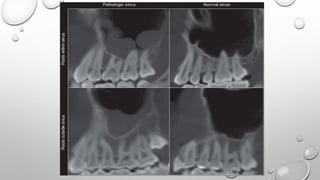

PERIAPICAL RADIOGRAPH

• BORDERS OF THE MAXILLARY SINUS APPEAR AS A THIN, DELICATE

RADIOPAQUE LINE .

• IN THE ABSENCE OF DISEASE IT APPEARS CONTINUOUS, BUT ON CLOSE

EXAMINATION IT HAS SMALL INTERRUPTIONS IN ITS SMOOTHNESS OR

DENSITY

• THE ROOTS OF MAXILLARY MOLARS USUALLY LIE IN CLOSE APPOSITION TO THE

MAXILLARY

SINUS AND MAY PROJECT INTO THE FLOOR OF THE SINUS,

CAUSING SMALL ELEVATIONS OR PROMINENCES.